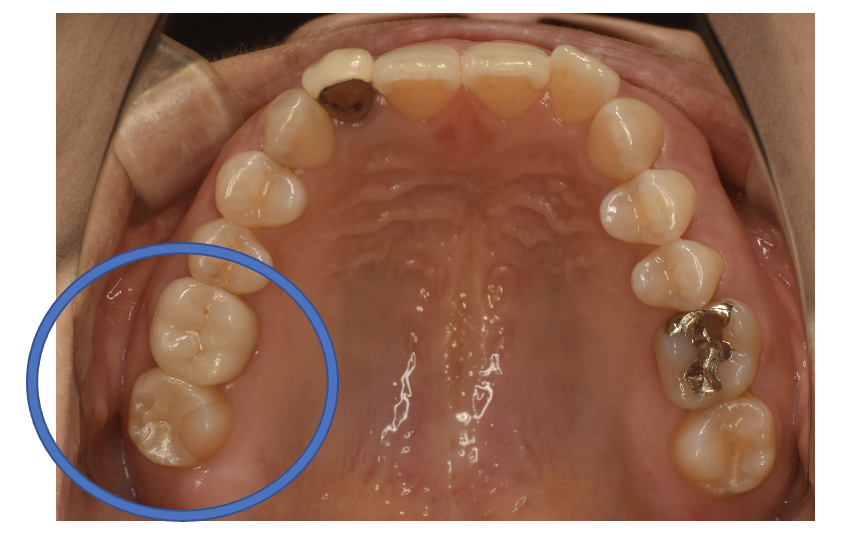

フルジルコニアIn 3 No.81

Before

After

| 治療方法 | フルジルコニアIn 虫歯などで失った歯質を天然歯と同じ色・質感のセラミックの一種であるジルコニア(人工ダイヤモンド)で補う治療法。 |

| 治療のデメリット | 変色がなく耐久性の高い治療ですが、歯周病や二次虫歯を予防するためには歯科医院での定期的なメインテナンスが大切です。 |

| 費用 | ¥69,000 |

| 通院回数 | 1ヶ月〜3ヶ月 |

| 備考 | 院長より 奥歯の、銀歯の中にむし歯が進行していたケースです。詰め物を選ぶ時には、見た目の自然さよりも、噛み合わせが強いことへの対応を 重視して、セラミックではなく、強度が強く人工ダイヤモンドとしても使用されるジルコニアインレーを選択することもあります。 |